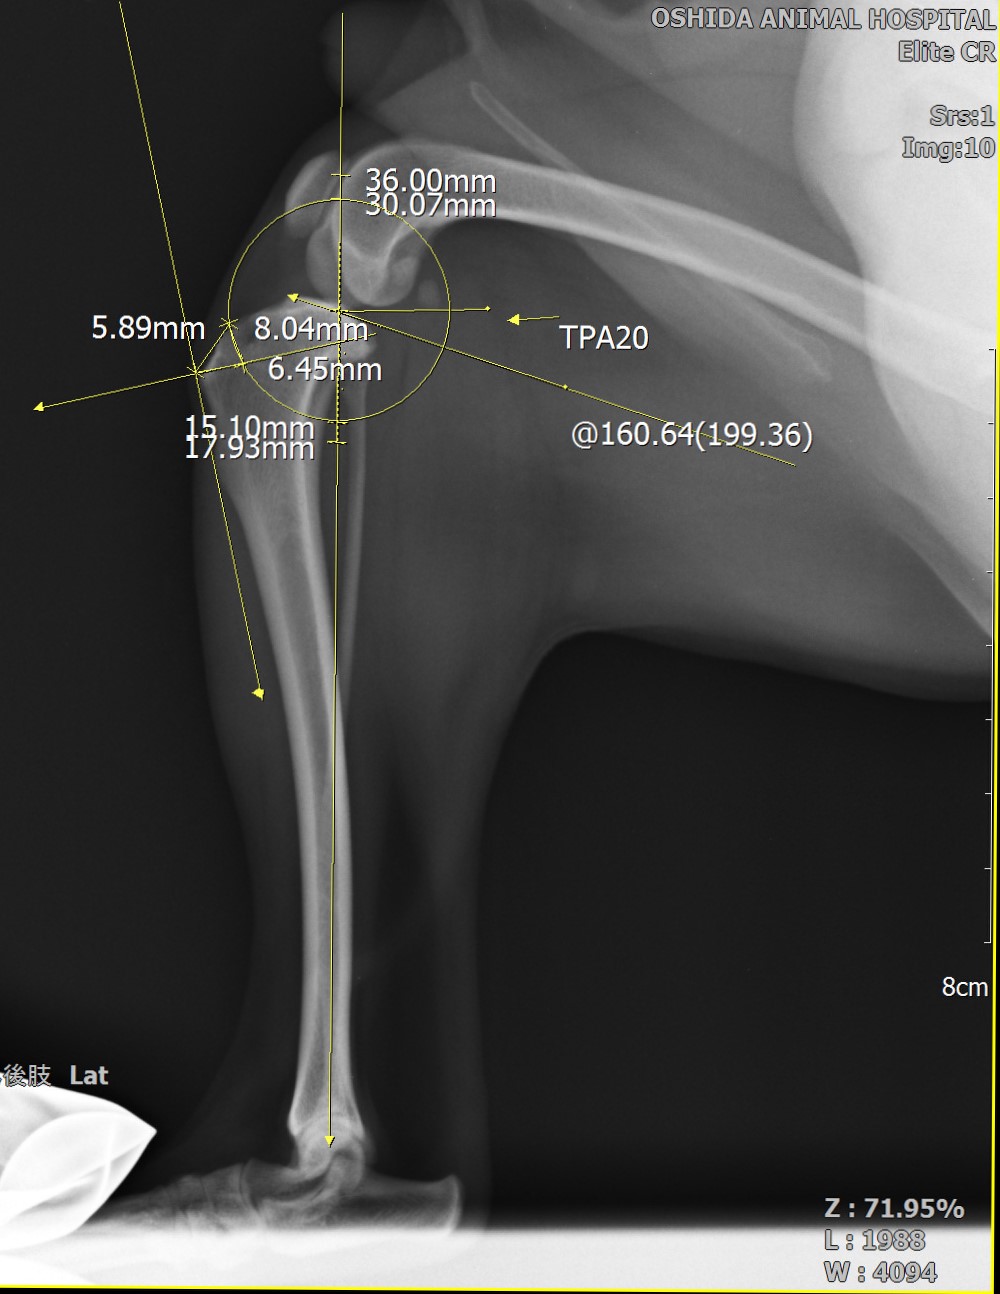

骨切りを行う前にインプラントの適応など入念な手術計画が必要です

TPLOをメインの手術手技として取り組んでいます。